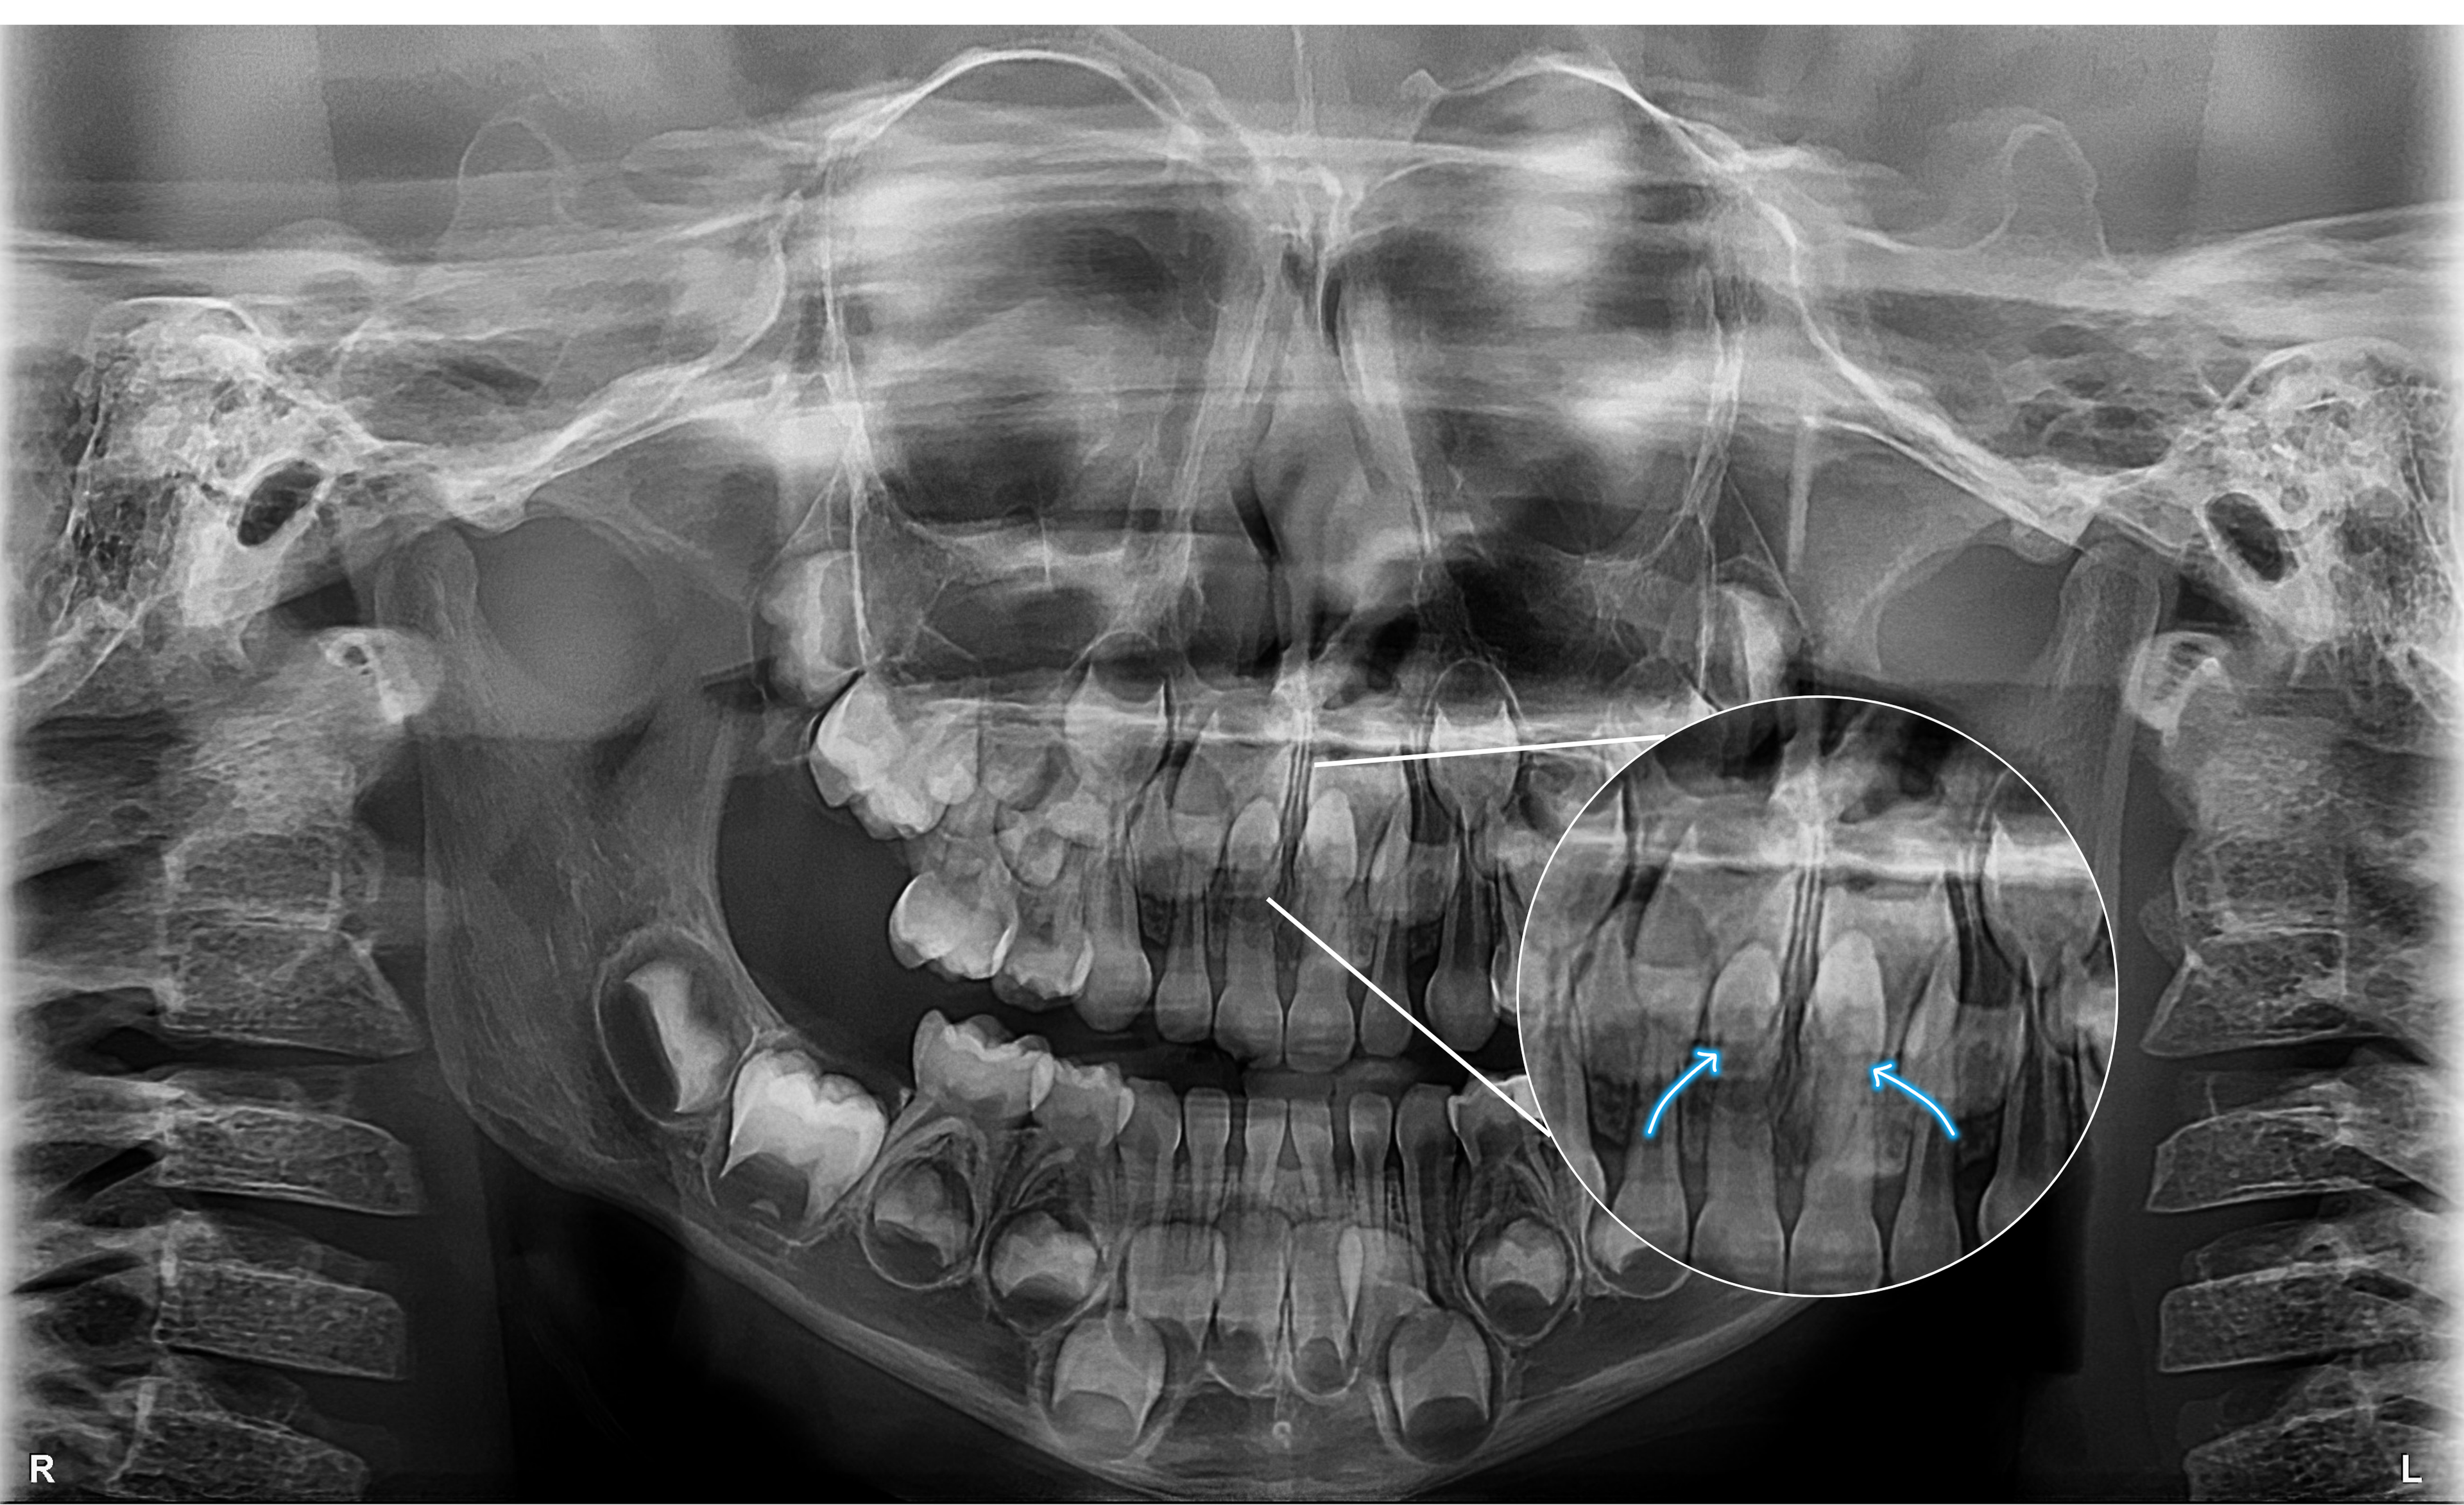

Na imagem panorâmica apresentada, observam-se dois dentes supranumerários localizados na região anterior da maxila, sobrepostos aos germes dos dentes 11 e 21 (incisivos centrais superiores).

• Localizar exatamente os dentes supranumerários;

• Avaliar sua relação com os germes permanentes;

• Evitar complicações cirúrgicas e garantir a preservação das estruturas anatômicas vizinhas.